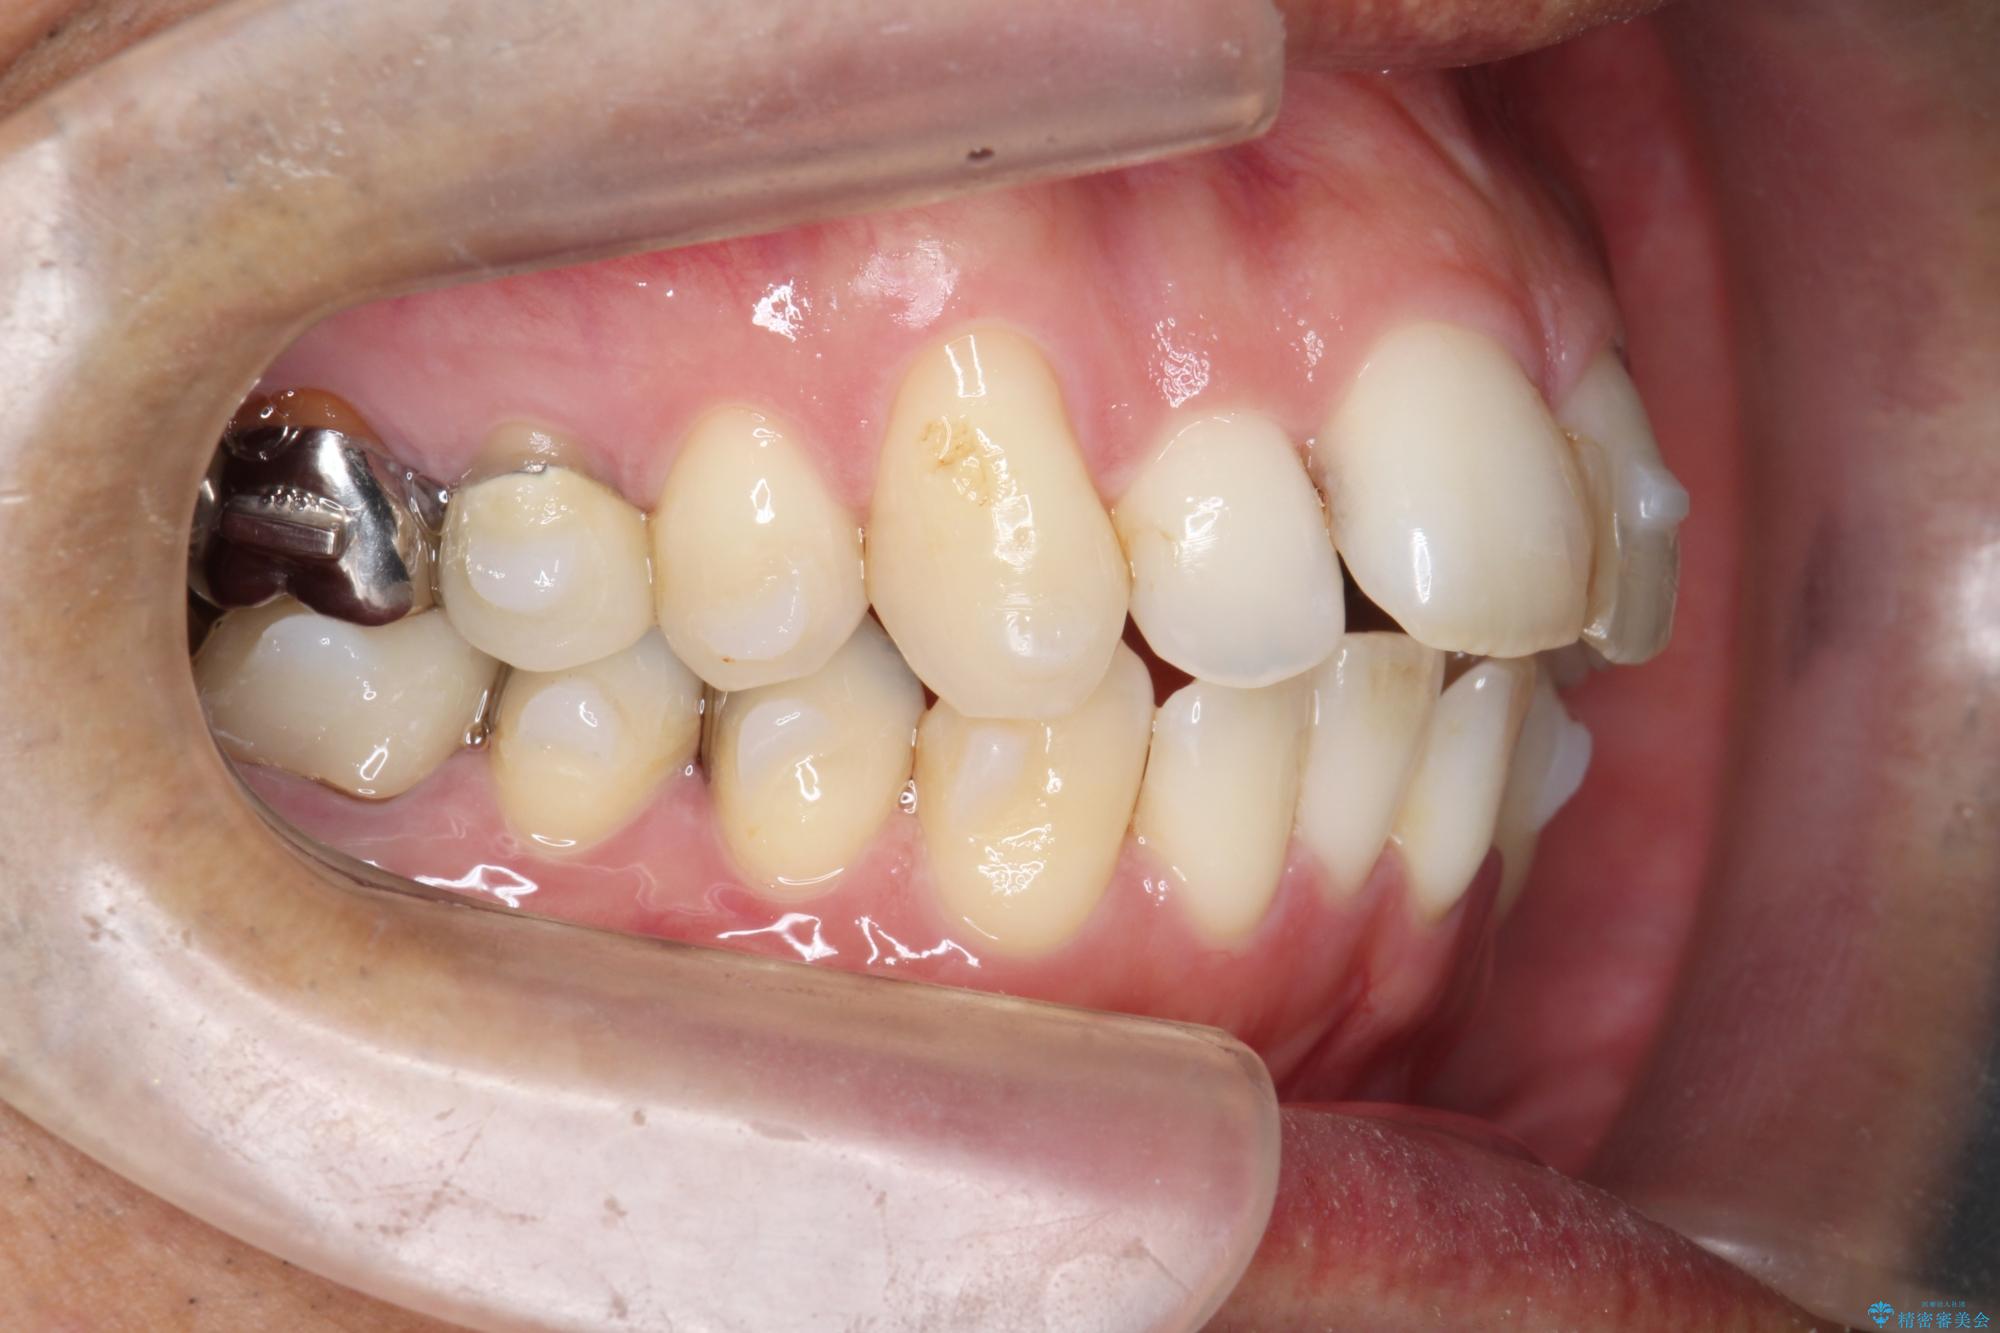

- 突き出た前歯の角度の改善と虫歯治療の改善を求めて来院されました。

虫歯を除去したのち、マウスピース矯正治療を行い、歯並びやがたつきを改善したのち、セラミックに置き換えることで審美性の向上を計画します。